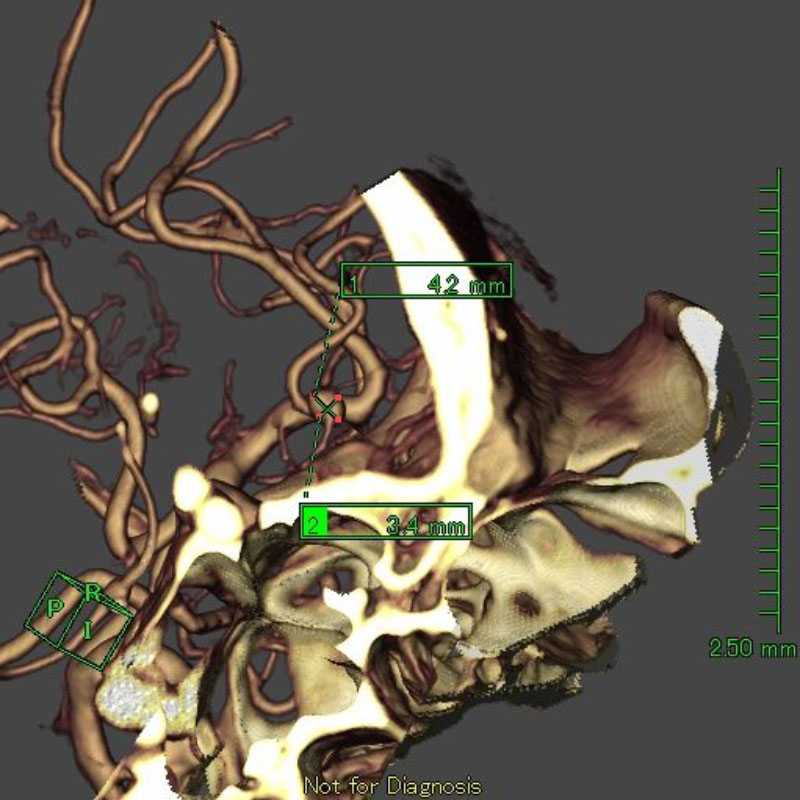

4

'25年1月

40代

右中大脳動脈瘤

クリッピング術

手術前

クリップ前

クリップ後

術後血管撮影